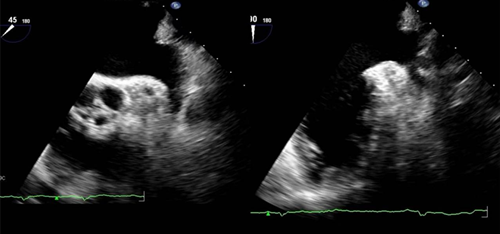

(经食管超声观察左心耳)

2.心脏占位性疾病:如心房粘液瘤、心腔内血栓等。

(经食管超声显示右房内血栓)

3.先天性心脏病,如:房间隔缺损、卵圆孔未闭等,常规经胸超声声窗差,不易准确诊断的病例,对于经胸超声不能明确房间隔缺损残端大小,或多发房间隔缺损患者,行TEE检查,可明确是否存在封堵适应证,并为封堵器大小的选择提供参考。

(经食管超声显示卵圆孔未闭)